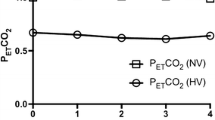

The breathing of the CO2-enriched gases was well tolerated by all patients. The physiological parameters are summarised in Table 3. FiO2 and PiCO2 values confirmed the tightness of the breathing system. PetCO2, being a rough measure for arterial PaCO2 [44], was significantly changed (p < 0.001, pairwise Student’s t-test) by 13 ± 3 mmHg for carbogen and by 16 ± 3 mmHg for CO2/air.

Results for the ROI response functions are given in Table 5, a typical plot of the temporal behaviour for different ROIs is given in Fig. 2. Comparing the two gases, it was found, that the observed changes were of the same order of magnitude but with partially different characteristics. For ‘non-tumoral’ tissue negative changes between −1.1 and −2.2 s-1 were found for both gases, with the exception of patient P2 (hypoperfused meningioma), in whom a large R2* decrease of -3.3 s-1 during carbogen was found. For ‘contrast-enhancing’ tumour areas, patients with a large negative R2* change (−3.4 s-1 for P1 under carbogen and -3.5 s-1 for P5 under CO2/air), patients with a medium-sized change (similar to that in ‘non-tumoral’ tissue) as well as patients with a small change (for the lymphoma P7) were found. The positive R2* changes in ‘necrotic’ areas and ‘oedemas’ were between +0.9 and +2.2 s-1.